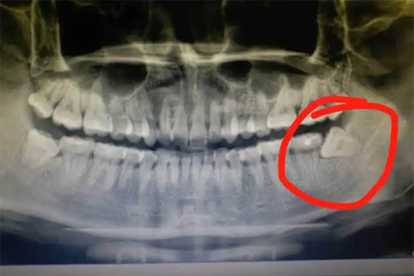

建议尽早就诊口腔外科检查,拍摄曲面断层片评估智齿位置与龋坏程度。术前需控制急性炎症,术后24小时内避免漱口或进食过热食物。日常应加强智齿区域清洁,使用单束牙刷或冲牙器减少菌斑堆积。